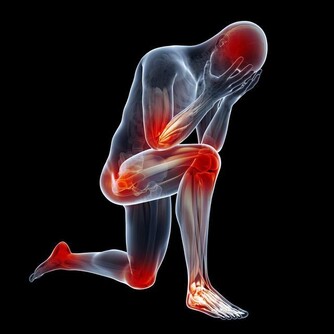

1.失眠,疲倦:

實際上,發生輕微的肝功能紊亂時,身體並不會出現一些比較明顯的症狀,但是這時候病人可能情緒的波動會比較大,進而就會影響到其睡眠質量和情況。肝臟出問題最明顯感覺就是疲憊,但是這種疲憊睡覺也無法解決,讓人找不到原因。肝功能不好的人主要原因是肝細胞受了損害,可致血清轉氨酶等酶類增高,而膽鹼脂酶降低,表現為乏力、易倦、思睡等。

5.體重下降,乏力:

當肝臟受損後,肝臟無法為身體提供能量,導致虛弱和肌肉萎縮,從而使得病人的體重發生驟減的現象。部分肝硬化早期可出現乏力、食慾減退,消化不良,噁心,嘔吐,右上腹隱痛和腹瀉等症狀。